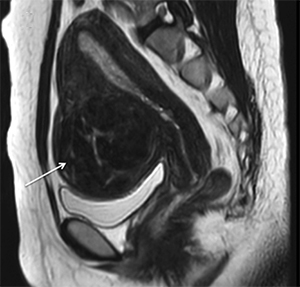

МРТ міоми

МРТ: вузол міоми на передній стінці матки

Це - безболісна процедура, що дає змогу фахівцям "бачити" розмір, форму, структуру матки, розташування вузлів та кровоток в них. У деяких випадках може бути необхідним трансвагінальне ультразвукове дослідження. У цьому разі датчик вводиться в піхву, що дає змогу чіткіше побачити внутрішню частину матки. Невеликий дискомфорт, пов'язаний із цією процедурою, окупається її високою інформативністю.

Лейоміома матки також може бути підтверджена за допомогою комп'ютерної томографії (КТ) і магнітно-резонансного дослідження (МРТ). Це також безболісні діагностичні процедури, що дають точну інформацію про кількість, структуру і розташування вузлів міоми.